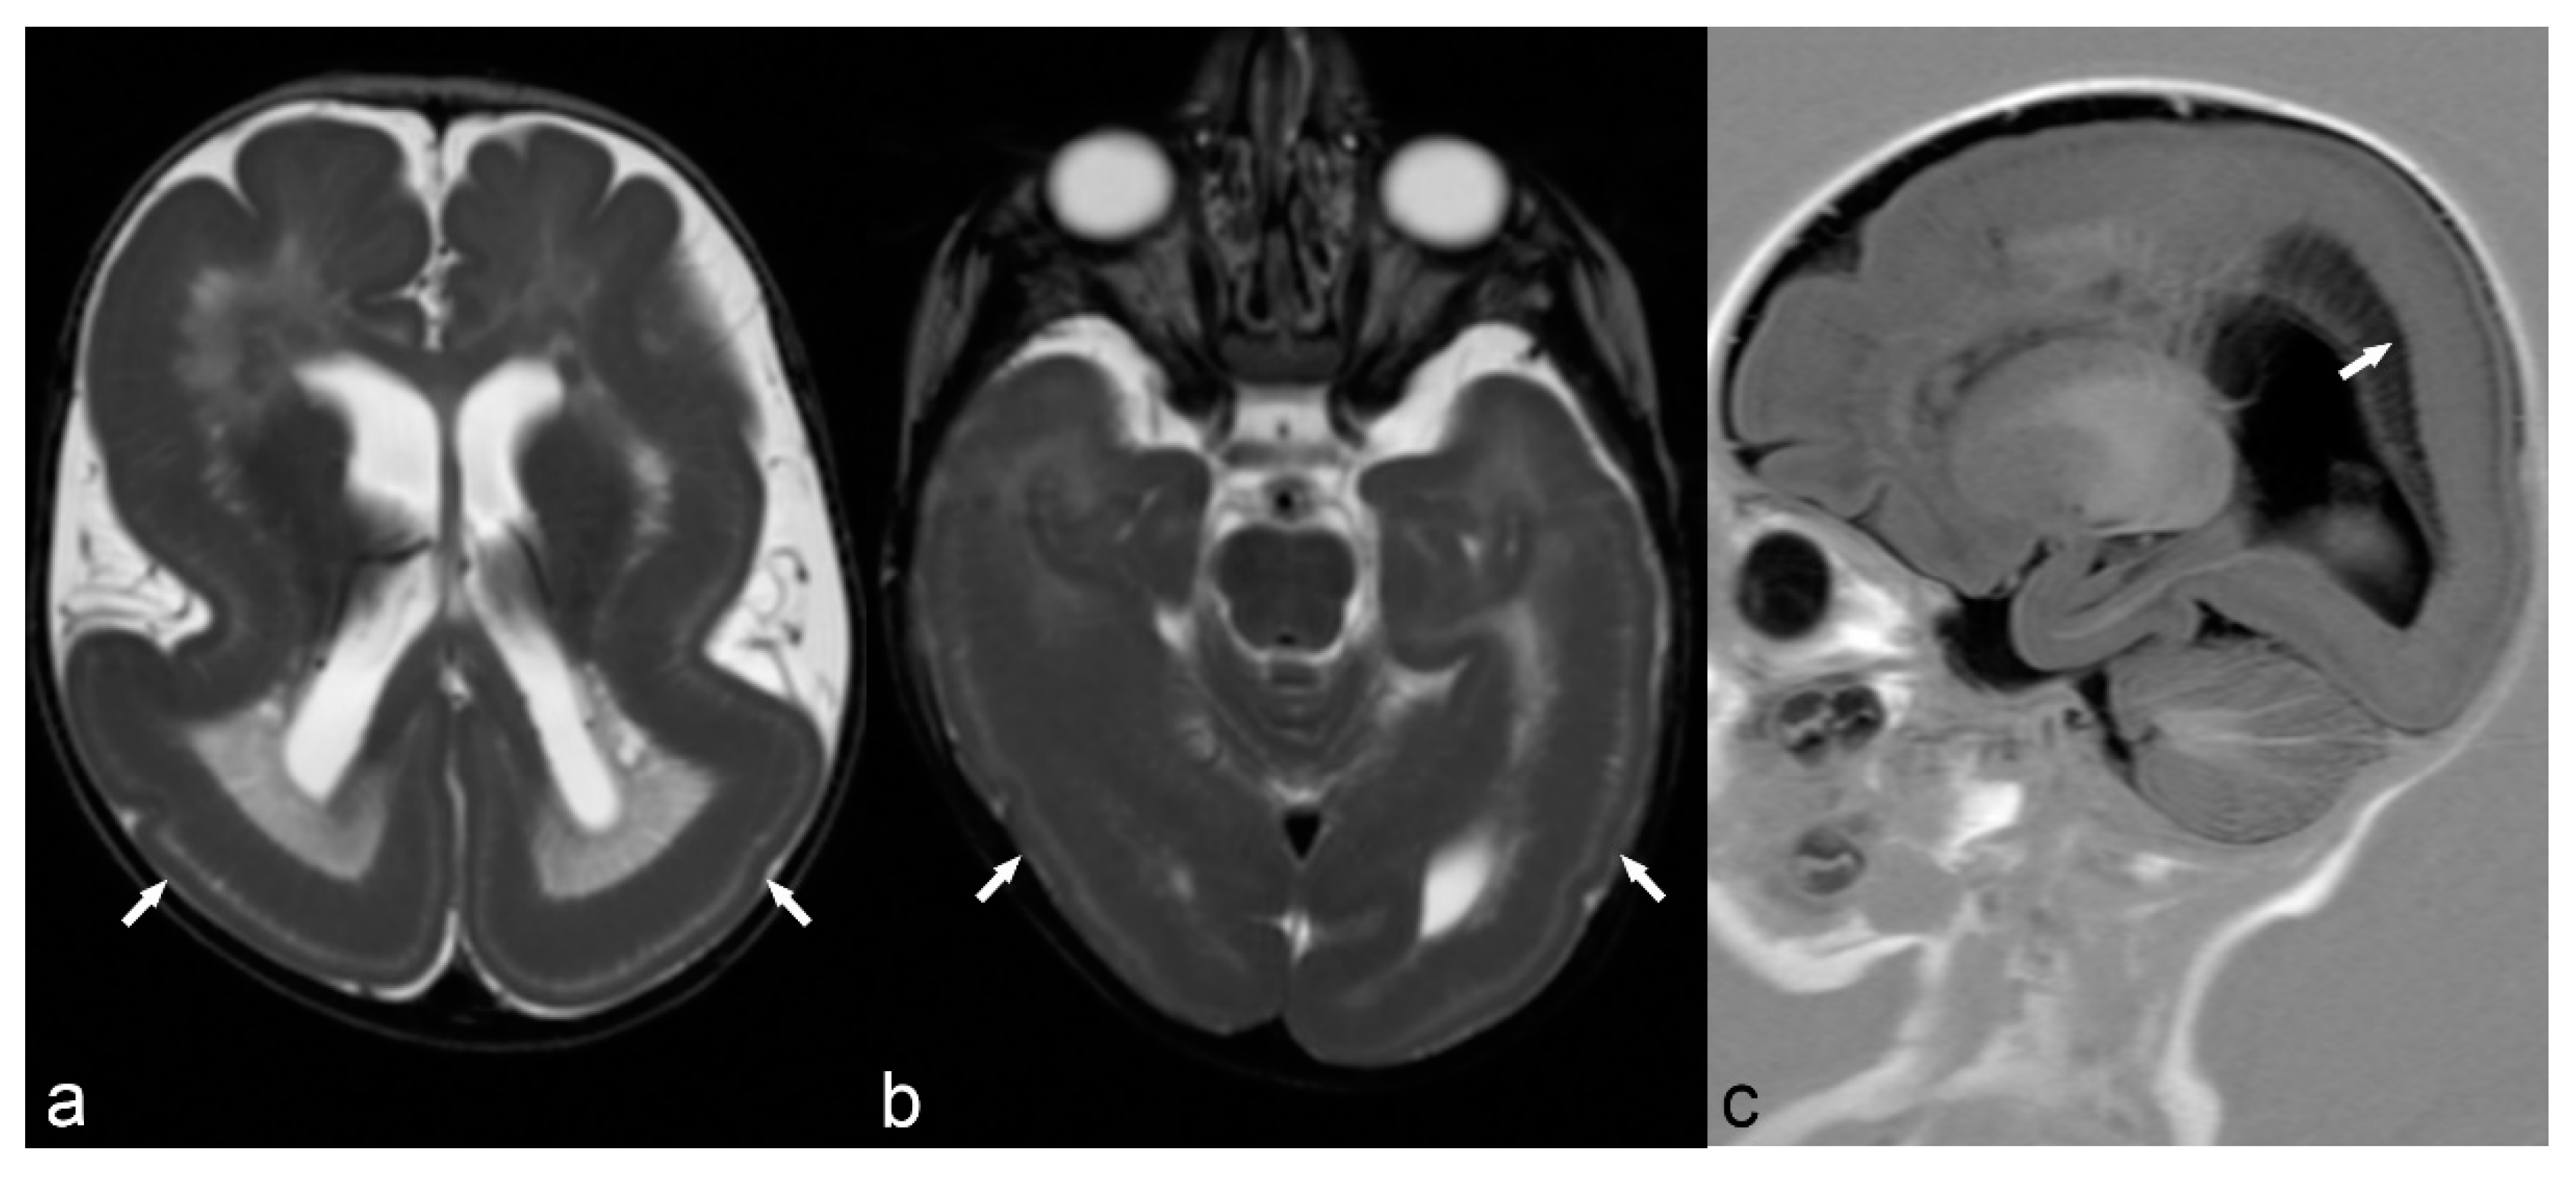

Figure 1.

33-year-old female with MERRF (myoclonic epilepsy with ragged red fibers) and myoclonic epilepsy. Axial T2 (a), Fluid-attenuated inversion recovery (FLAIR) (b) and Diffusion weighted imaging (DWI) (c) trace images (b = 1000) show cortical thickening in the right frontal (arrow) and bilateral pericingulate region (arrowhead) with subcortical white matter hyperintensity and restricted diffusion (ADC images not shown). Magnetic Resonance (MR) spectrum (d) at short TE (35 ms) at the level of right pericingulate lesion (region of interest of 1 cm diameter) shows lactate peak at 1.33 ppm (curved arrow) consistent with mitochondrial encephalopathy.